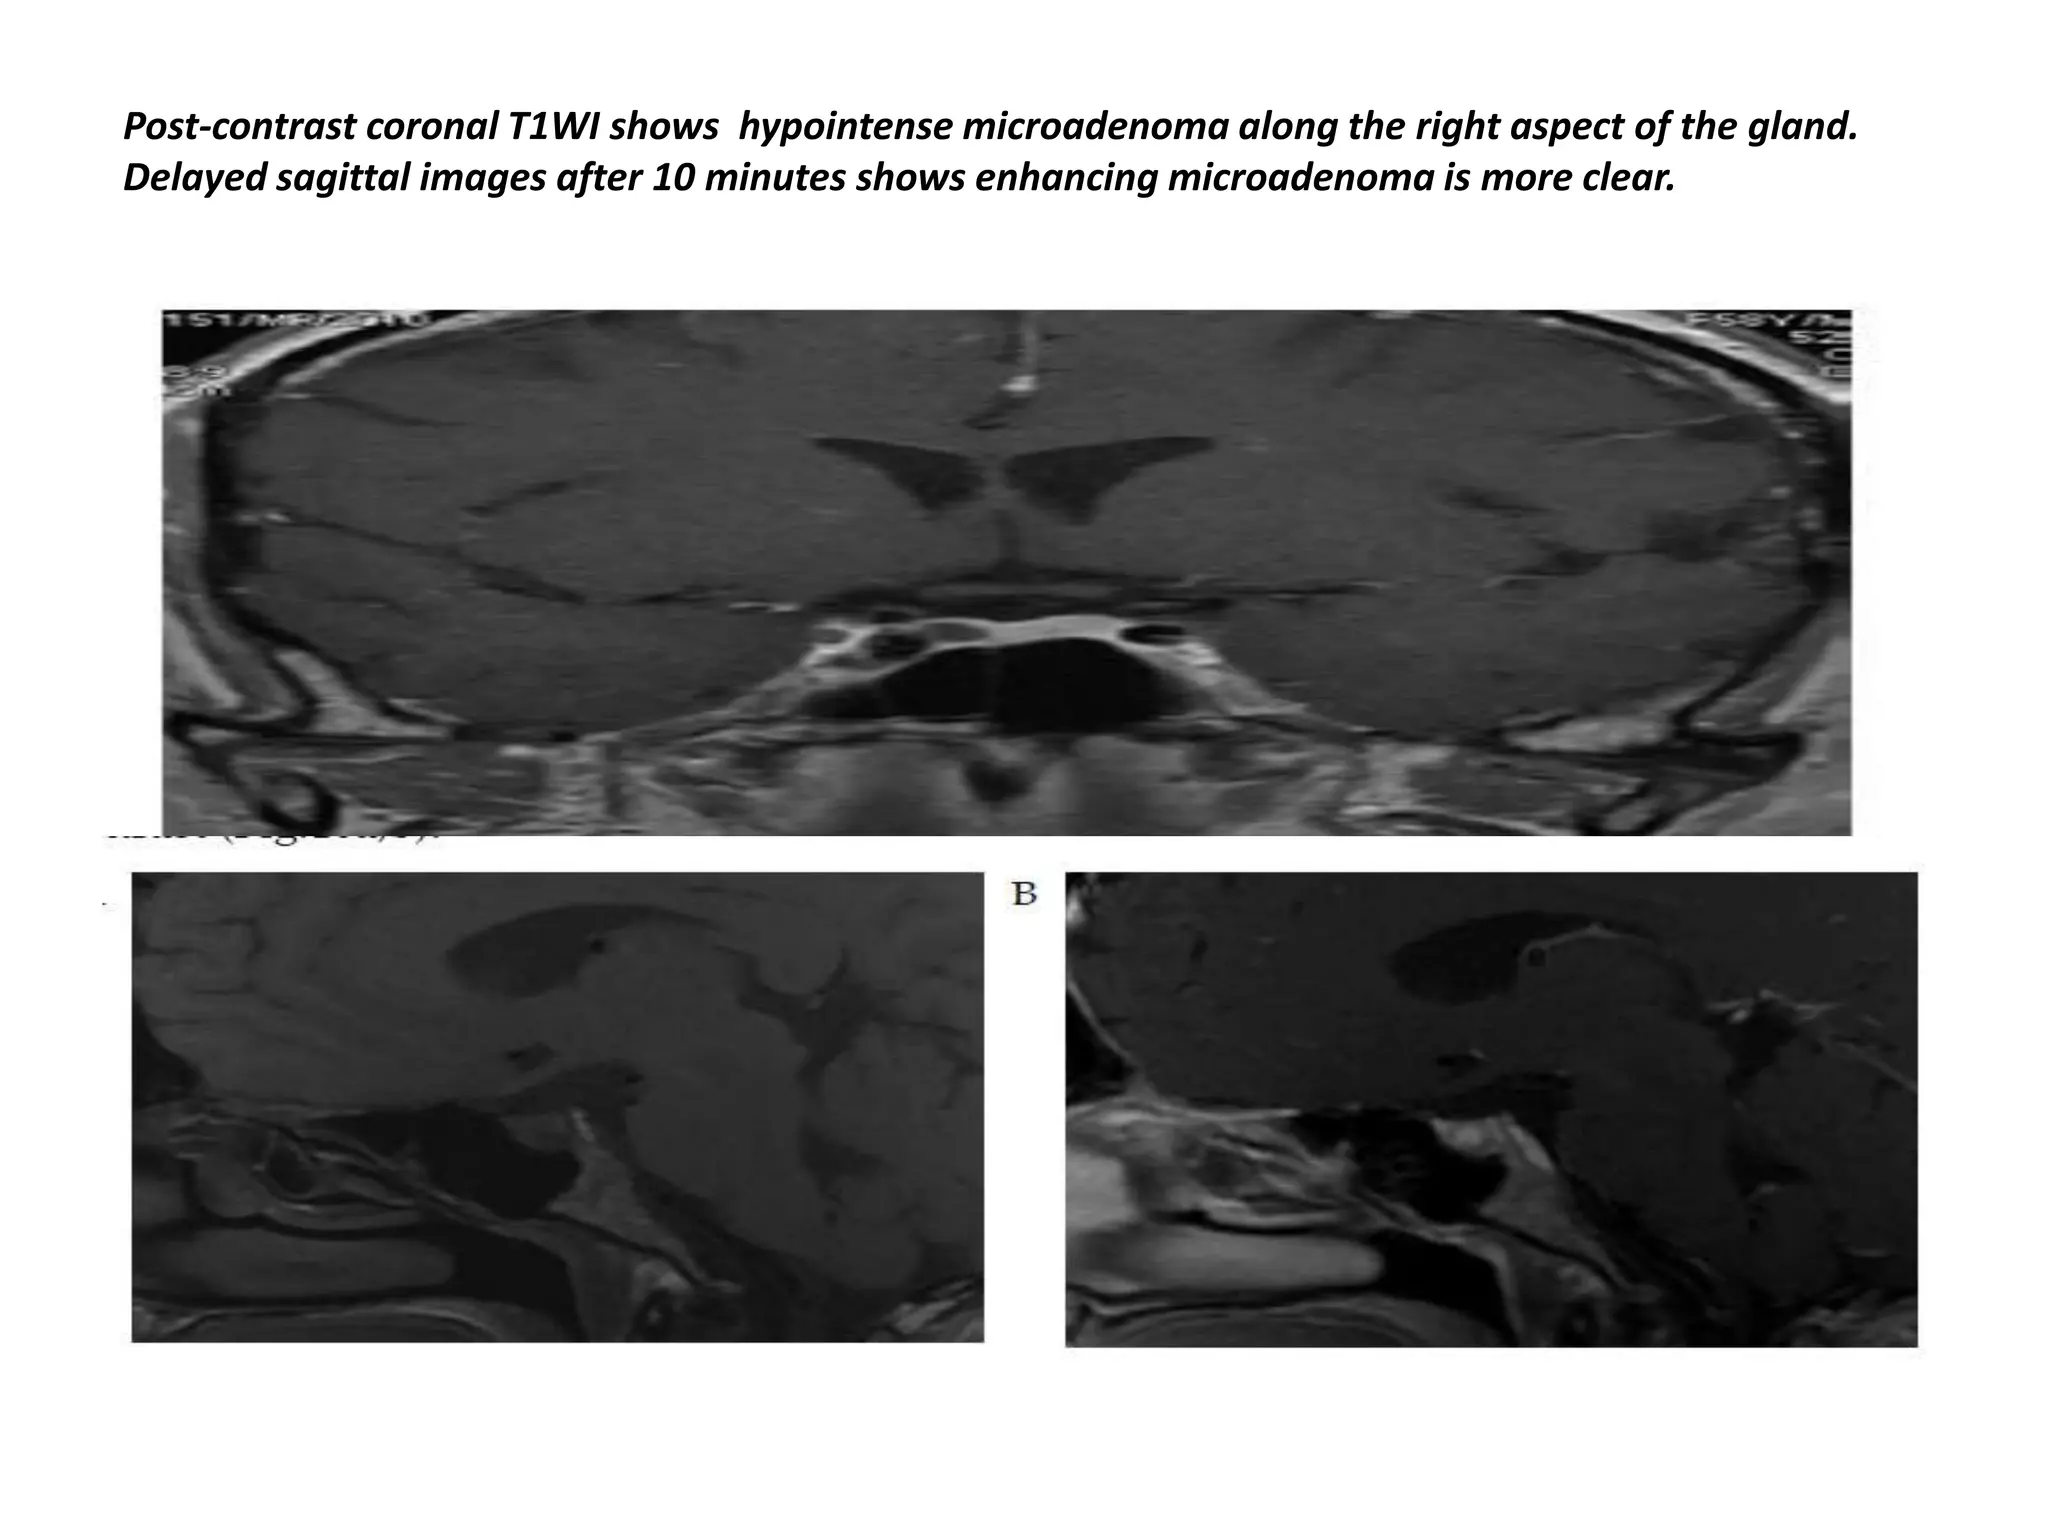

Post-contrast coronal T1WI shows hypointense microadenoma along the right aspect of the gland.

Delayed sagittal images after 10 minutes shows enhancing microadenoma is more clear.

Post-contrast coronal T1WIshows hypointense microadenoma along the right aspect of the gland. Delayed sagittal images after 10 minutes shows enhancing microadenoma is more clear.